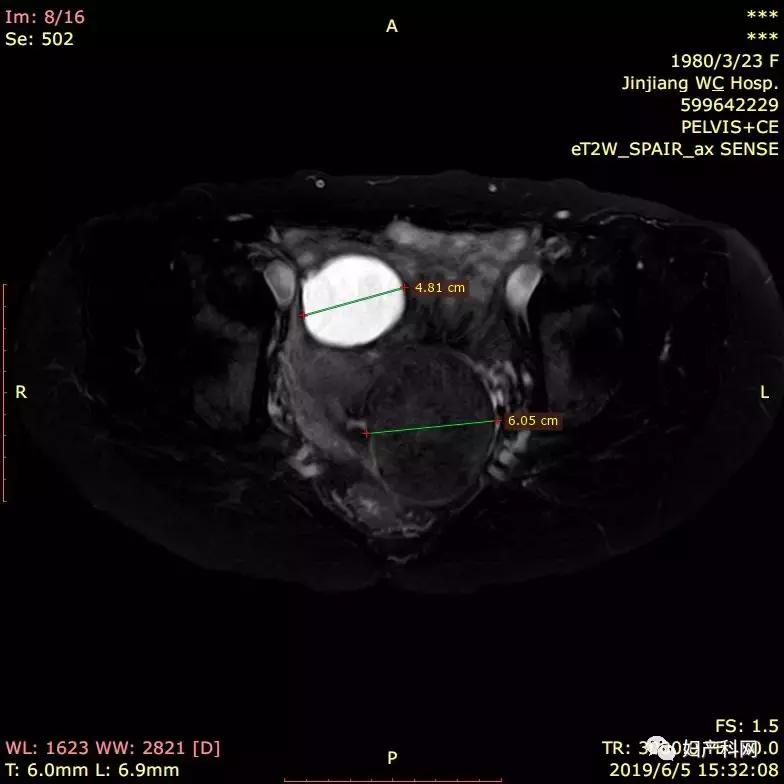

2005年和2013年腹腔镜卵巢囊肿手术各一次,病理均为子宫内膜异位囊肿,3年前复诊时发现子宫肌瘤,同时发现卵巢囊肿术后复发,均未做治疗,现因自觉小便次数多,贫血就诊。在2005年和2013年两次手术时医生均提到“腹茧症”。平素月经:7-10天/26-30天,痛经(-),量偏多,用1-2包卫生巾。MRI(2019.6.6):1、子宫颈肌瘤5.2*6.2*6.9cm。2、子宫前方囊性占位4.1*4.9*6.6cm,倾向良性。宫颈刮片(2019.4):正常。2019年4月HB 94g/L

我们给这位客人选择的治疗方式为经皮卵巢囊肿穿刺+无水酒精固化+经皮子宫肌瘤微波消融术。术中从右侧卵巢囊肿内抽出褐色液体约70ml,使用无水酒精20ml固化15分钟后抽出。子宫肌瘤原本预计经阴道穿刺,但因为子宫肌瘤位置较偏,阴道穿刺后评估安全性存在问题,改为了经皮穿刺,60w功率下消融了18分30秒,子宫肌瘤基本达到完全消融。

通常囊肿穿刺我们都是从阴道进行,因为大部分时候从阴道超声可以直接的接触到卵巢囊肿,避免对周围组织的损伤,但是对于像本例中的这样的情况,因为子宫肌瘤以及多次手术的影响,盆腔粘连比较厉害,若是做腹腔镜手术,相信会是一场粘连的噩梦,经阴道穿刺又难以触及到囊肿。这样的情况,就需要适当的做出调整,改为经腹的穿刺,当然仍然需要仔细评估穿刺路径是否安全。

宫颈的肌瘤本来是计划经阴道穿刺,但因为微波消融针仅有14g,韧性也稍差一些,对于这样位置的子宫肌瘤,虽然可以进行穿刺,但对于消融针的位置控制却比较困难,多次尝试后,虽然能够正常穿刺入宫颈的肌瘤,但均难以达到满意的位置,这样做消融势必存在部分肌瘤被漏掉的问题,难以做好消融的适形性。这也回答了之前部分医生提出的为什么不从阴道做消融治疗的问题,对比下来,经腹穿刺在控制性上会灵活很多,当然需要术前仔细的评估,特别是要注意肠道的影响。